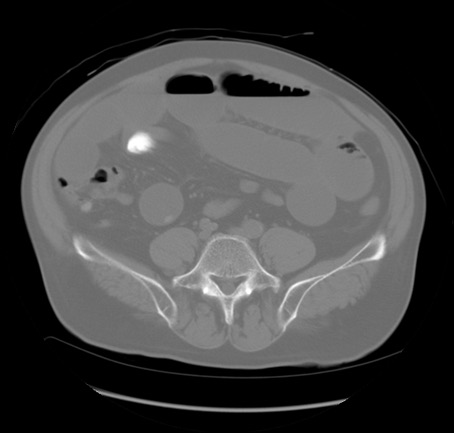

冠状断像

矢状断像

【症例】 60歳代男性

【主訴】 腹部膨満、嘔吐

【現病歴】5日前頃より倦怠感を認め食事量減少し4日前の朝嘔吐、食事摂取困難となった。 3日前近医受診し点滴施行され整腸剤などを処方された。 当日他院を受診し、腹部膨満著明、炎症反応の上昇(CRP10.8、WBC11200)あり、紹介受診となる。

【身体所見】 意識JCS1 受け答えがはっきりしないBP 111/57mHg、 P 67bpm、、BT35.2°C、SpO2 97%(RA)、 腹部:膨隆、打診で鼓音あり、全体的に圧痛有り、腸蠕動音(-)、反跳痛ははっきりせず。

【データ】WBC 11400、CRP 14.20